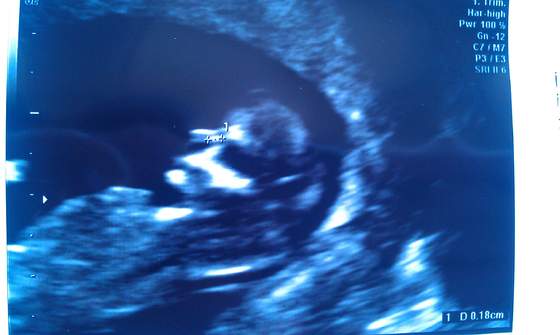

Właśnie wróciliśmy z wizyty. Dzidziuś ma już 5cm, przezierność i nosek ok. Wierzgał podczas badania i wypinał się pupcią do pani doktor.

Jedynie serduszko mu szybko bije :-( FHR 179 i z tego powodu powinnam zrobić test Pappa (szalenie drogi) ale to da nam wiadomość o zdrowiu dziecka

tak, w prywatnej przychodni. Na ekranie dzidziuś prezentował się jeszcze lepiej, ale zdjęcia są takie żeby dr mogła wykonać odpowiednie pomiary